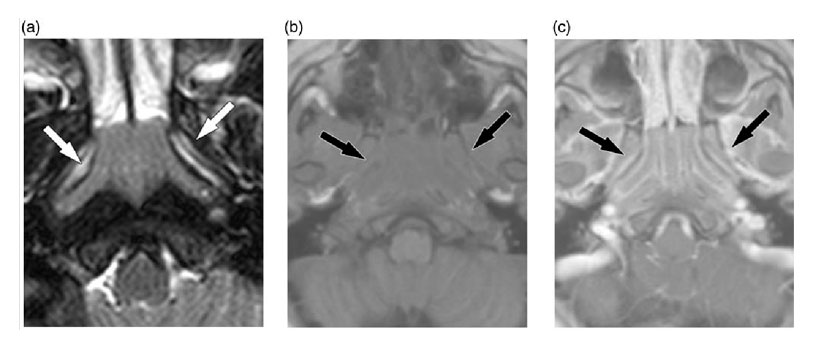

Surov A, et al, realizaron un estudio con el objetivo de identificar la frecuencia de HA y analizar sus hallazgos en la RM en diferentes grupos de edad. Desde 2007 hasta 2011, se realizaron 6693 exámenes de RM. La RM se obtuvo con un dispositivo de RM de 1,5 T. Se identificó HA en el 18,0% de los pacientes, la frecuencia varió de 60.3% a 1.0% en los diferentes grupos de edad; el tamaño medio de la HA fue de 23,2 ± 4,5 mm en sentido cráneo-caudal, 31,1 ± 5,2 mm en sentido de izquierda-derecha y 14,2 ± 4,1 mm en la dirección anterior-posterior. Los tamaños izquierdo-derecho y cráneo-caudal de fueron mayores en el grupo de 0 a 9 años y disminuyeron con la edad.

En las imágenes T1-w, la mayoría de las lesiones (95,4%) fueron hipointensas en comparación con la musculatura adyacente. En las imágenes saturadas de grasa T2-w, el 82,4% de las lesiones eran hiperintensas. Después de la administración intravenosa de medio de contraste, la mayoría de las lesiones mostraron una ligera mejoría (58,6%). Se observó una mejora moderada en el 32,4% y se identificó una mejora marcada en el 9,0%. En el grupo de 0 a 9 años de edad, la mayoría de las lesiones mostraron una leve mejoría. Se identificaron quistes dentro de la HA en 433 casos (35.9%). La frecuencia de los quistes aumentó continuamente con la edad, es decir, del 10,9% al 65,2%.